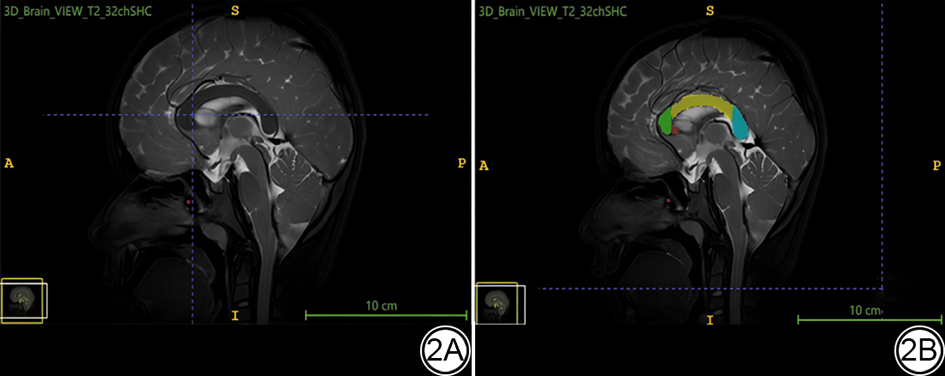

参照FA图,ADC图、彩色编码FA图及T1解剖像,基于Witelson七分法于放大的正中矢状切面图像上选取CC嘴部、膝部、体部、压部做为研究对象,即以线段连接CC最前端和最后端,于CC最前端和最后端连一线段,然后以垂直这条线段的5条垂线(二等分、三等分及五等分)划分CC,分为七区(CC1–CC7:1区为嘴部,2区为膝部,3区至6区为体部,7区为压部)(图1)。于CC的正中状切面,以最小体素形测量工具,分别于嘴部、膝部、体部、压部勾画ROI,使其均处于解剖部位中心,为减少测量误差对统计结果的影响,对各参数三次测量数据取平均值(图2)。

图2  脑矢状面视图。2A:脑矢状面视图原始图,2B:ROI被标记后图像,红色代表CC嘴部,绿色代表CC膝部,黄色代表CC体部,蓝色代表CC压部。DTI:弥散张量成像;ROI:感兴趣区;CC:胼胝体。

Fig. 2  The sagittal view of the brain. 2A: The original sagittal view image; 2B: The image with the ROI marked, red indicates the rostrum of the CC, green represents the genu of the CC, yellow denotes the body of the CC, and blue marks the splenium of the CC. DTI: diffusion tensor imaging; ROI: region of interest; CC: corpus callosum.